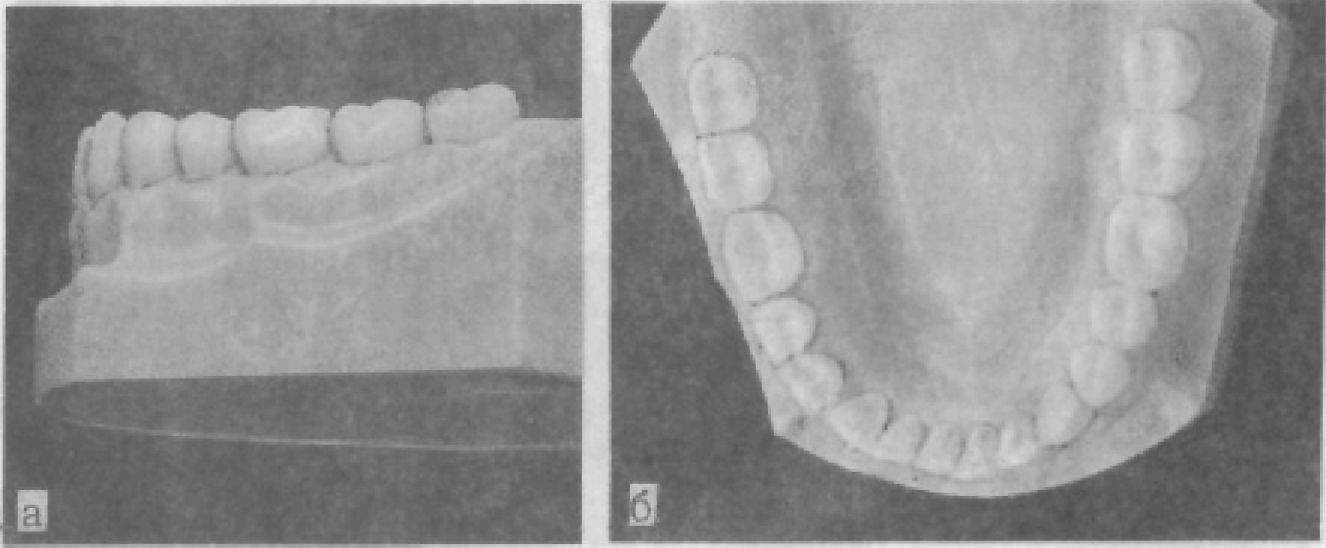

В ряде случаев можно отметить отсутствие контактов вследствие аномалии развития зубов и челюстей, удаления зубов (рис. 16),

кариозного поражения или неправильно наложенных пломб, искусственной коронки. Отсутствие контакта может являться симптомом патологической перестройки в костной ткани челюстей при смещении зубов под влиянием жевательного давления.

Рис. 16. Изменение в зубных рядах при частичной потере зубов.